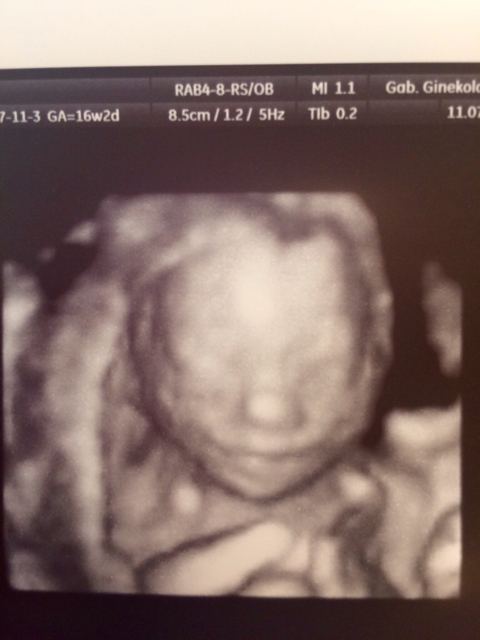

ciężaróweczki po in vitro